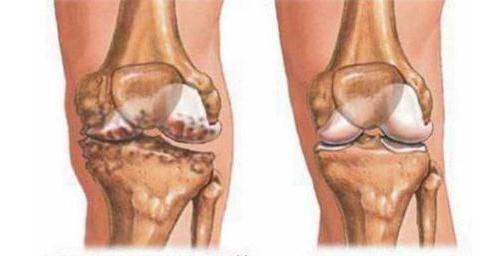

Причинами разрушения хрящевой ткани могут быть перенесенные в анамнезе инфекционные или кристаллические артриты (ревматоидный, реактивный артриты, подагра, псориатические артропатии), острая или хроническая перегрузка сустава (спортивная, весовая), травма, гиподинамия у возрастных больных. Все это вызывает нарушение метаболизма, снижение уровня протеогликанов, потерю воды. Хрящ разволокняется, иссушивается, трескается, истончается. Происходит его разрушение, потом регенерация с потерей конгруэнтности, начинает оголяться и разрастаться костная ткань. При отсутствии лечения суставная щель пропадает, кости соприкасаются. Это вызывает острую боль и воспаление, деформацию, некроз кости.

Рентгенографию коленного сустава делают в боковой и прямой проекциях. К рентгенологическим признакам артроза относится: уменьшение высоты суставной щели, костные разрастания, остеофиты, остеосклероз субхондральный, кисты в эпифизах, деформация.